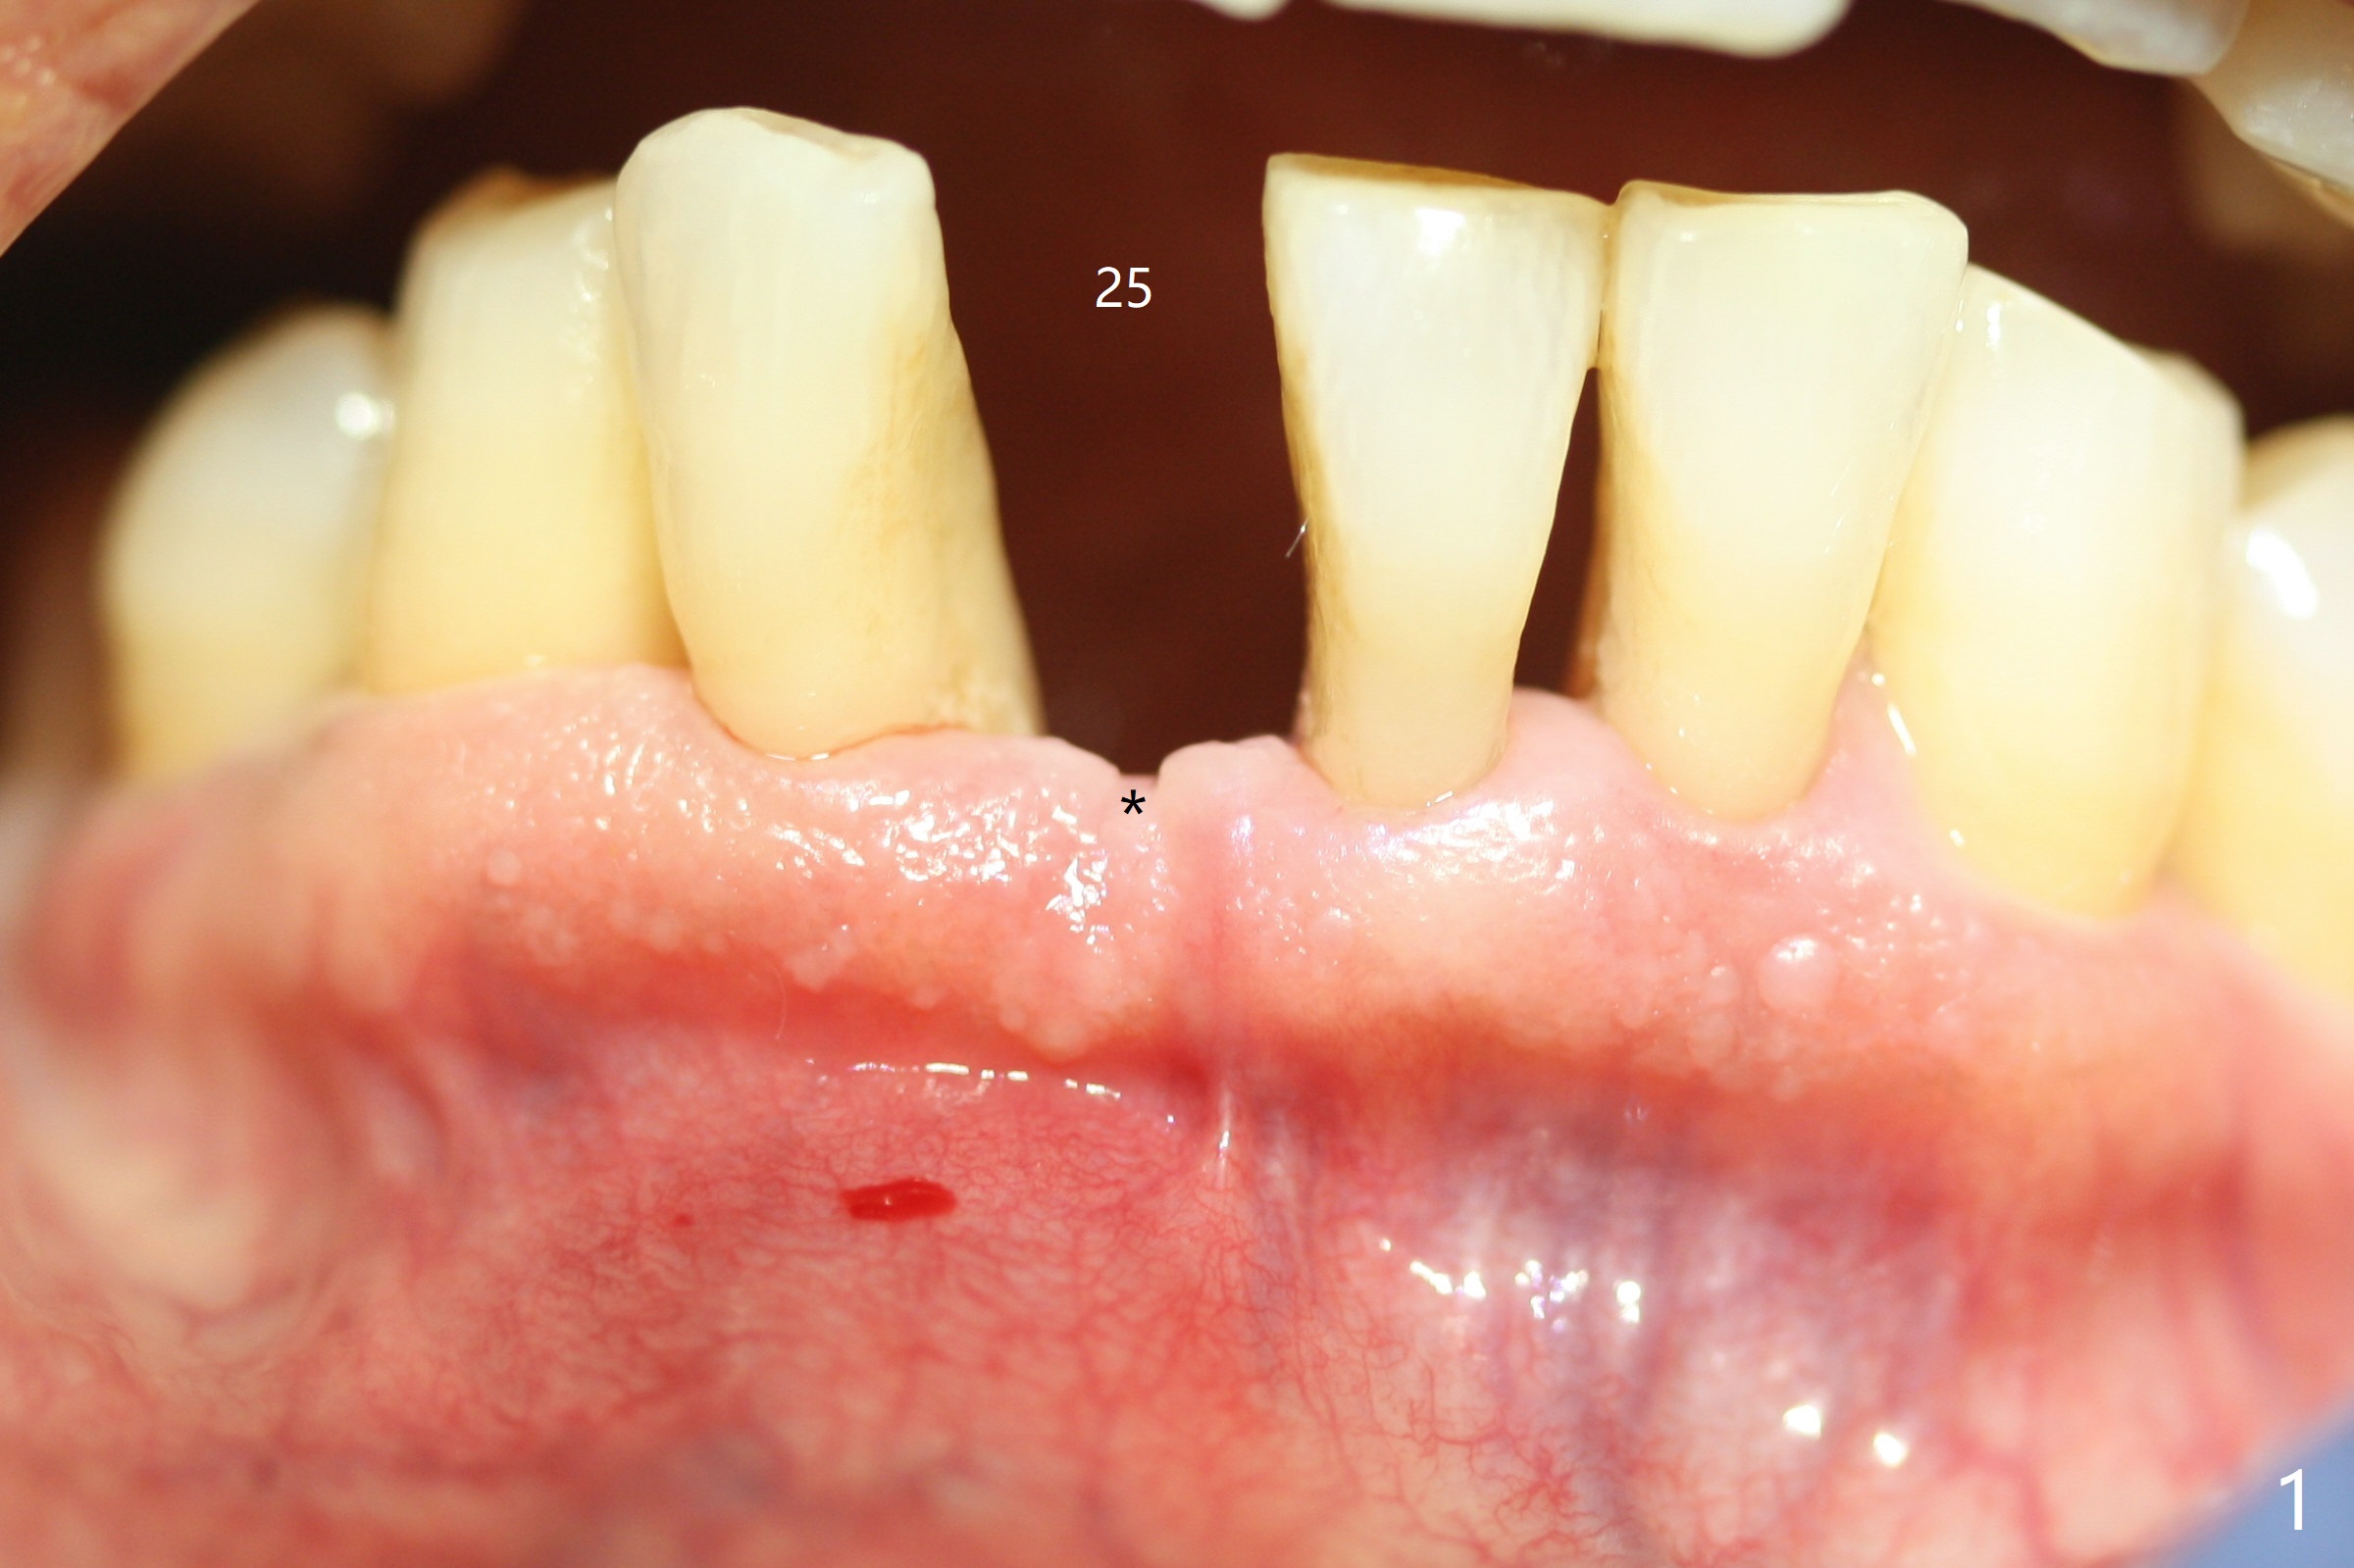

Out of financial concern, the patient does not agree to have the tooth #26 extracted. Due to atrophy of the most coronal ridge buccally at #25 (Fig.1,2 *), osteotomy is initiated difficult and distal (Fig.3). After 1.2 mm drill removal (Fig.3' black area), Lindamann bur is used to move the osteotomy mesial (red area). A 2x12(4) mm 1-piece implant is placed (Fig.4,5); the buccal defect is packed with allograft (Vanilla, .5-1 mm cancellous/cortical mixture, *). When the tooth #26 fails, a 2 mm implant will be placed (Fig.6 blue). Following abutment adjustment, a provisional is fabricated (Fig.7 P); note the lower incisal edges of #25 and 26, as compared to those of the neighboring teeth. To reduce occlusal trauma, the incisal edge of the tooth #26 has been decreased (Fig.5 open arrow). The implant threads seem not to be exposed 4 months postop (Fig.8), although the tooth #26 has mobility II.